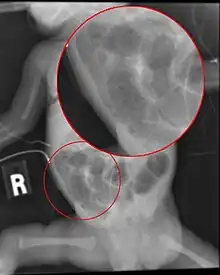

Diagnosis is usually suspected clinically, but often requires the aid of diagnostic imaging, most commonly radiography, which can show the intestines and may show areas with dead tissue or a bowel perforation.[18] Specific radiographic signs of NEC are associated with specific Bell's stages of the disease:[19]

- Specific radiologic signs (pneumatosis intestinalis or portal venous gas)

- Severe radiologic signs (pneumoperitoneum)

Alimentary tract of infant showing intestinal necrosis, pneumatosis intestinalis, and perforation site (arrow) (autopsy)

Close-up of intestine of infant showing necrosis and pneumatosis intestinalis (autopsy)